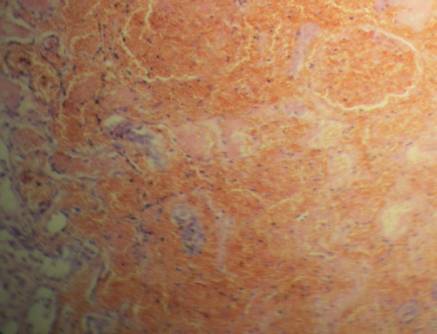

кількість лімфоідних інфільтратів, виявляються поодинокі гістіоцити. Через 2-3

доби після заподіяння травми починаються ознаки організації: в стромі виявляється

наростання лімфогістіоцитарної інфільтрації, що відображено на рисунку 2,

починається утворення тонкостінних судин зі стінок капілярів. В даний термін

Рис. 2. Вогнищева гістіоцитарна інфільтрація. Забарвлення гемотоксилин-еозіном. Х 200.